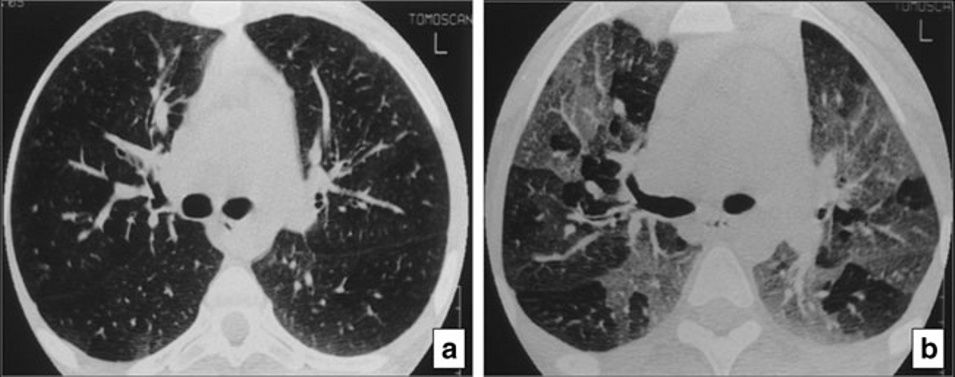

10、马赛克征

这种模式的特征是增加和减低的密度混杂拼凑,这可能代表(1)分布不均的间质性疾病,(2)闭塞性小气道疾病和(3)闭塞性小血管疾病 。经典疾病:闭塞性细支气管炎(OB)。

*囊性纤维化患者的闭塞性细支气管炎。在(a)吸气和(b)呼气时在隆突水平进行HRCT在呼气时显示“马赛克衰减模式”,其次空气滞留征(b),在吸气时未显示(a)

鉴别疾病:慢性血栓栓塞性肺动脉高压可能由于斑片状的血管性低氧血症而表现出马赛克征。亚急性超敏性肺炎也可能表现出马赛克衰减模式,既表现为“间质性”病因,表现为衰减增加的区域(磨玻璃影不透明),又表现为“小气道疾病”病因,表现为衰减减少的区域,可能加剧。呼吸性细支气管炎也可能是这种模式。